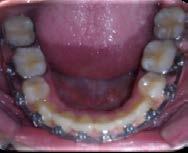

La paciente concluyó su tratamiento en diciembre de 2016, el tratamiento activo duró 3 años. La retención elegida fue un circunferencial en superior e inferior un fijo de premolar a premolar.

Figura 11. Fotografías intraorales finales.